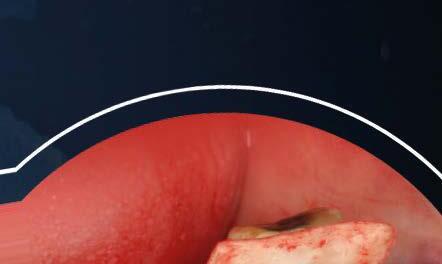

Se realiza una incisión biselada hacia coronal a espesor total en forma de parábola cóncava a apical en la mucosa labial con una hoja de bisturí no 10 alejada del fondo de vestíbulo actual. Es necesario destacar que la línea de incisión que estamos realizando se convertirá en el nuevo fondo de vestíbulo al final del procedimiento. El bisturí debe estar orientado a 45o al eje apico-coronal de los dientes. Además, la extensión mesio-distal de la incisión será acorde al número de recesiones adyacentes a tratar, debiendo extendernos idealmente un diente más a cada lado.

Una vez preparado el lecho receptor, dada la existencia de una situación combinada de recesión gingival y una dehiscencia ósea vestibular con pérdida de inserción interproximal, se opta por la utilización combinada de un injerto de tejido conectivo autólogo tuberositario, un sustituto de origen alogénico (Lámina de cortical desmineralizada Cortiflex® Salugraft Dental) que se fija mediante dos chinchetas a ambos lados, cubriendo un injerto óseo de origen alogénico particulado (OraGRAFT® Aloinjerto Cortical Particulado MIX 70% Mineralizado / 30% Desmineralizado). Primero se suturó el injerto de tejido conectivo autólogo al colgajo, después se colocaron las partículas

de injerto óseo y, posteriormente, se fijó la lámina cortical.

Por último, se sutura la línea de incisión a fondo de vestíbulo dando puntos anclados al periostio, permitiendo, con escasos puntos de sutura, cerrar el acceso realizado y dejando la mucosa labial cicatrizando por segunda intención.

Estos puntos se dan atravesando con la sutura el colgajo en dirección corono-apical y, posteriormente, atravesando el periostio en perpendicular en dirección mesio-distal.